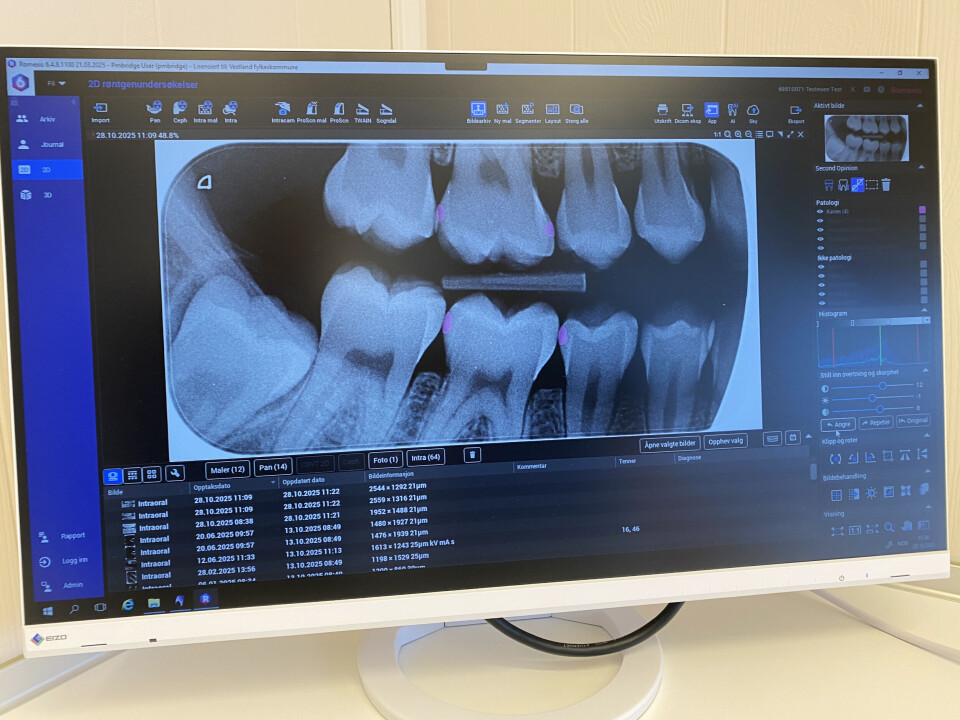

Klinikkleiar Dorte Grønsberg (bak) ved Sogndal tannklinikk ser på vurderinga frå KI-systemet i lag med ein tannpleiar.

Område med mistenkt karies vert rosa på røntgenbileta.

Namnet på verktøyet er «Second Opinion» og skal gje nettopp ei «second opinion» – ei ekstra vurdering – etter at tannlækjaren har vurdert saka manuelt. Analysen tek berre 30–40 sekund og resulterer i rosa og grøne fargefelt der KU «mistenkjer» høvesvis karies eller tannstein. I tillegg er verktøyet godt eigna til å visa beinnivå.